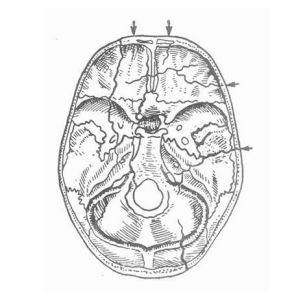

6、顱骨平片了解顱骨骨折的部位、類型、移位情況、顱內金屬異物或嵌入物的位置等。